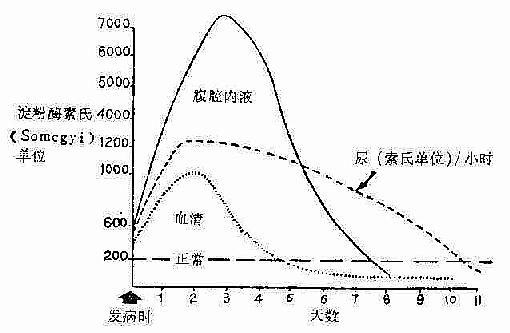

急性胰腺炎病人胰淀粉酶溢出胰腺外,迅速吸收入血,由尿排出,故血尿淀粉酶大为增加,是诊断本病的重要的化验检查。血清淀粉酶在发病后1~2小时即开始增高,8~12小时标本最有价值,至24小时达最高峰,为500~3000Somogyi氏单位,并持续24~72小时,2~5日逐渐降至正常,而尿淀粉酶在发病后12~24小时开始增高,48小时达高峰,维持5~7天,下降缓慢(图2-77)。

图2-77各种体液内淀粉酶值,在血清淀粉酶恢复正常时,尿淀粉酶仍高。

淀粉酶值在严重坏死型者,因腺泡严重破坏,淀粉酶生成很少,故其值并无增高表现。如淀粉酶值降后复升,提示病情有反复,如持续增高可能有并发症发生。有时腹膜炎,胆道疾病,溃疡穿孔、绞窄性肠梗阻、胃大部切除术后输入袢梗阻等,淀粉酶值可有不同程度的增高,但一般多低于500苏氏单位。因此,当测定值>256温氏单位或>500苏氏单位,对急性胰腺炎的诊断才有意义。